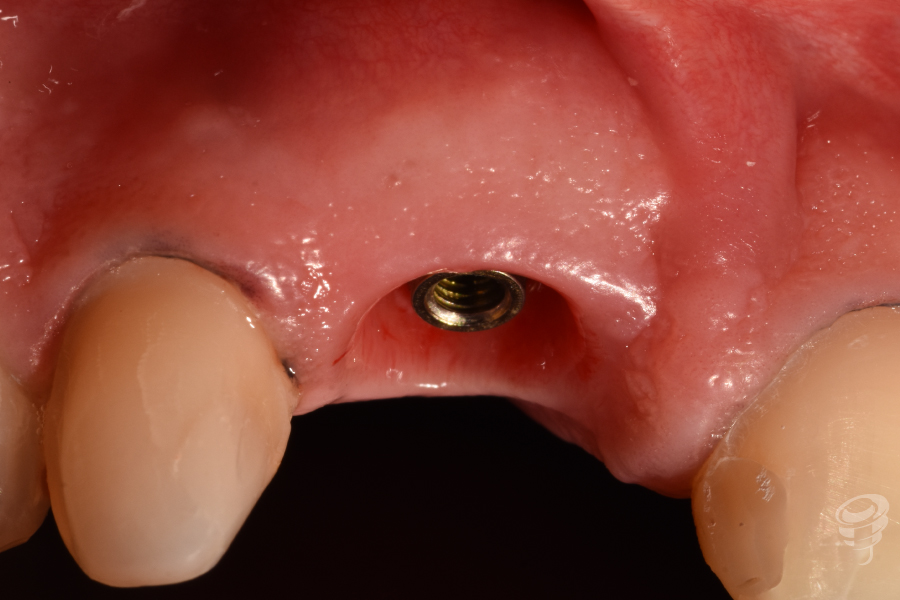

Fase 2: Controles y Segunda Etapa (Mes 4)

- Confirmación de osteointegración (ISQ > 70).

- Impresión convencional para realizar un encerado diagnóstico estético y posteriormente una realización de réplica del perfil de emergencia con la técnica de Hinds, para solapar una medida convencional con una digital (escáner intraoral).